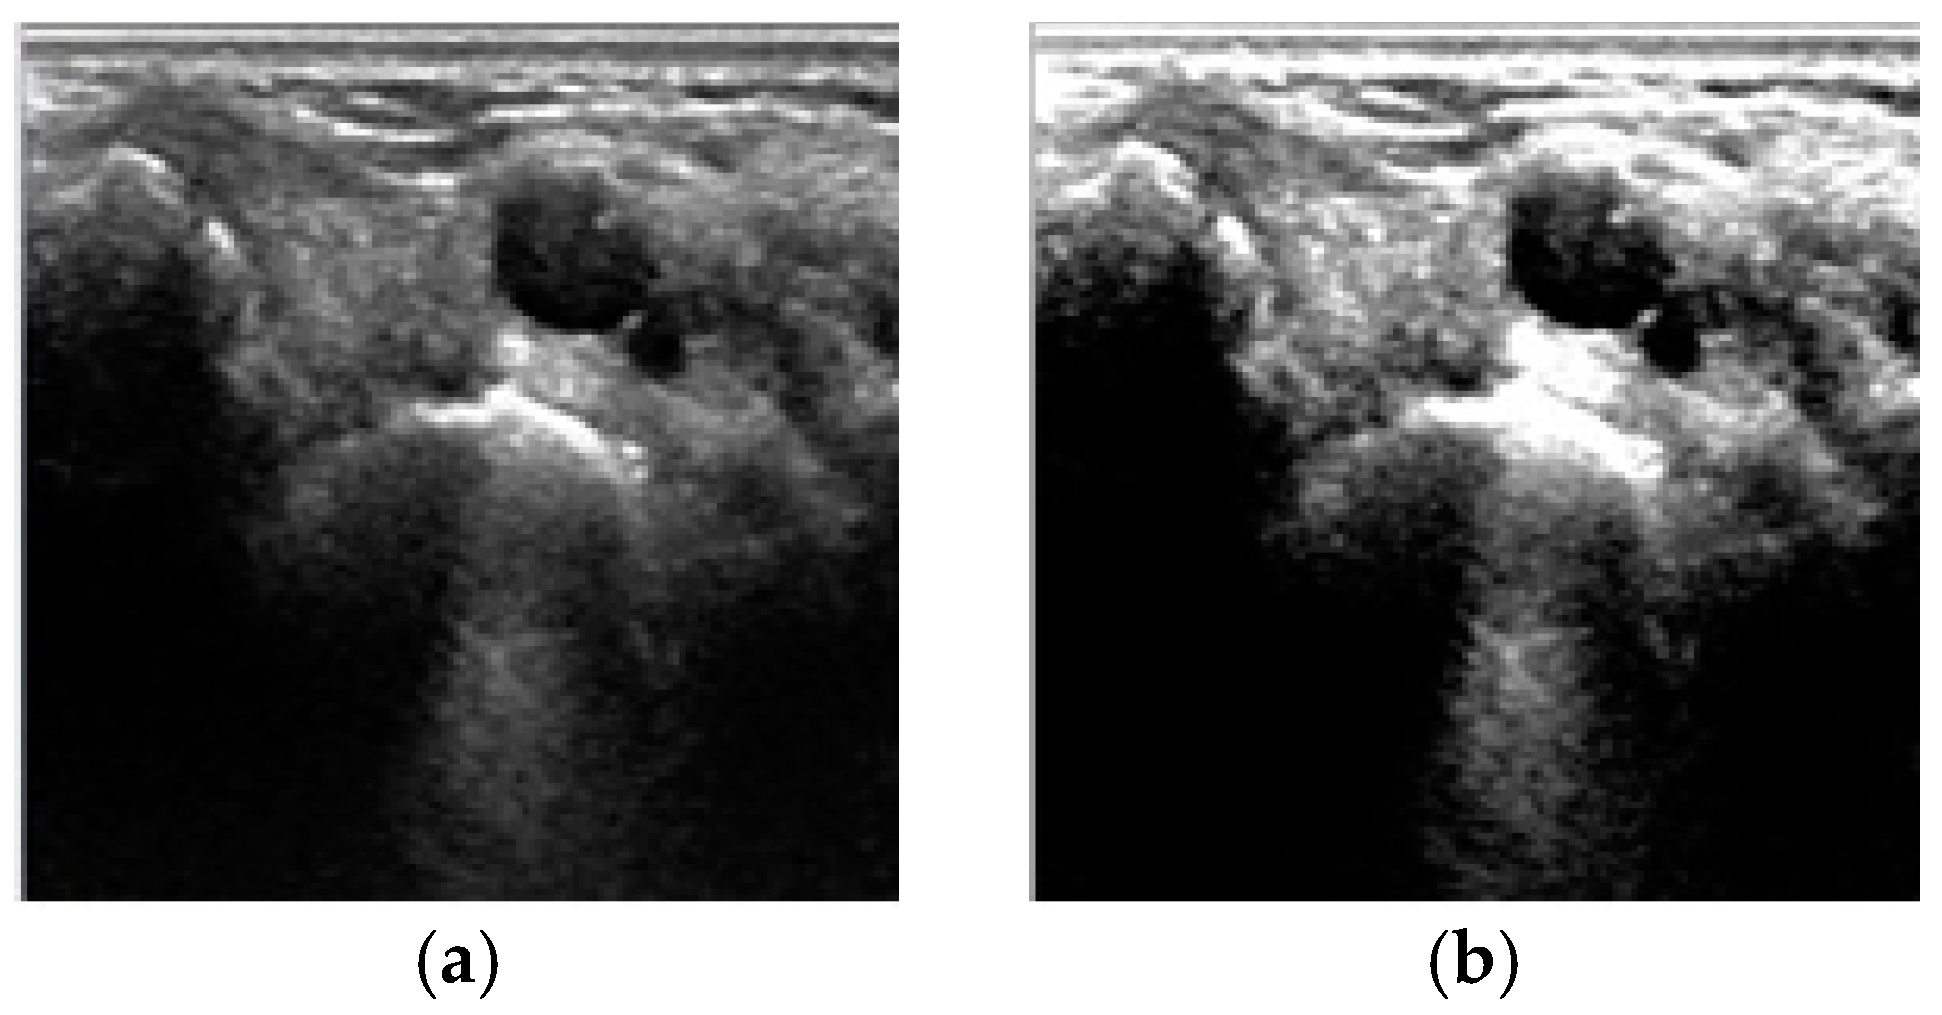

1. Introduction

2. Fuzzy Stretching with Trapezoid Membership Function in Image Enhancement

4. Results and Discussion